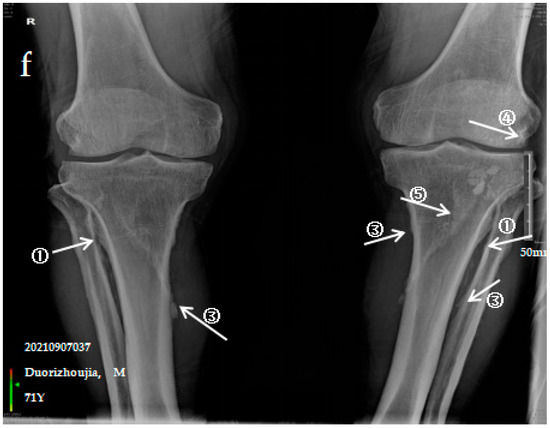

3.2.3. Case Analysis of a Patient Diagnosed by X-ray with Severe SF